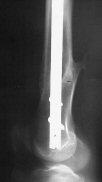

Attached are few examples from our Hospital:

A. Difficult reductions, even in retrograde nailing (my preference, easier control of "small" distal fragment) and it is much, much harder to do it anterograde (Alex, do you have one good case in your collection of anterograde nailing in very distal fractures - as you have suggested that I

should have done it in my previously posted case?

Malpositioning is much too common (recurvatum, varus - valgus).

B. Fixation loosening: distal cutting of the nail, non-unions do happen (cases attached).

Locking Plating has more distal screws than any nail, fixed angles and provides much better fixation, especially in osteoporotic bone.